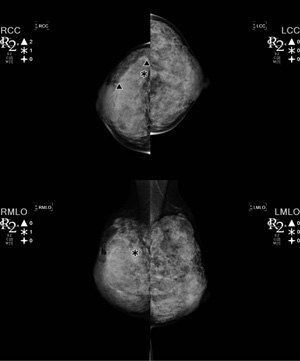

HOLOGIC社の一部門であるR2 Technologyが開発したSenova CADは,読影医の負担軽減に資することが期待される(図5)。

図5 Senova CADの表示例